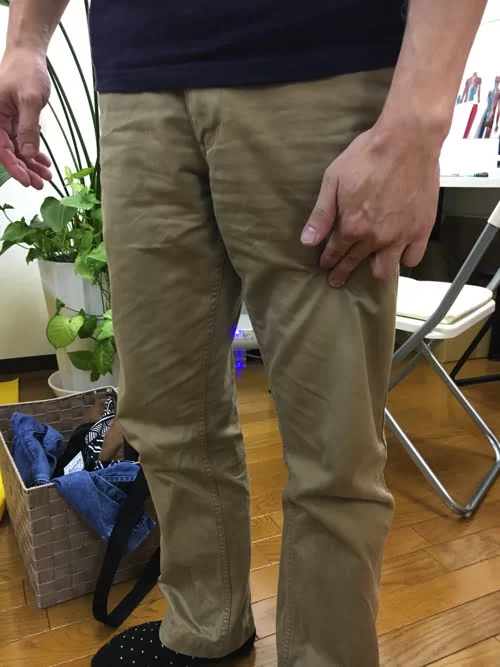

痛みの場所はここ。

そして脚の前側にも痛み

膝下のここにも痛み。

そして足先はシビレがある状態でした。

動いた際に違和感を感じる部分はここと

ふくらはぎ。

そして足裏。

お身体の状態を診させて頂くとこんな感じでした。